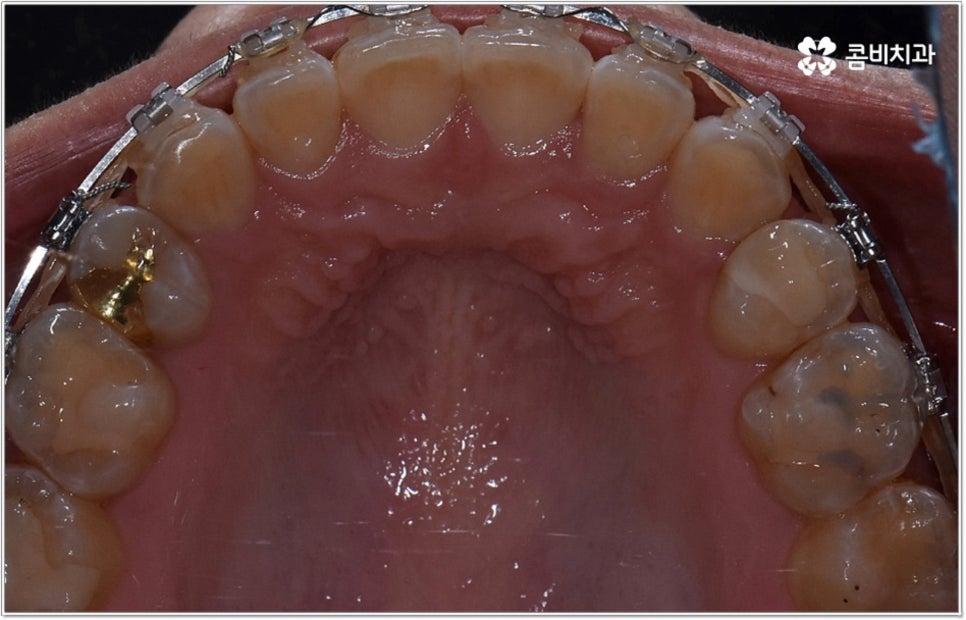

잘 아시다시피 교정이란 치아에 교정 장치 (브라켓) 를 부착하고 와이어에 교정력을 걸어 필요한 방향으로 치아를 이동시킴으로써 고른 치열과 올바른 교합을 가진 정상적인 구강 구조를 회복하는 치과 진료를 의미하는데요, 말씀드린 것처럼 부정교합에는 다양한 형태가 있고 또한 환자분들마다 심각한 정도가 모두 다르기 때문에 현 상태를 면밀하게 체크하고 맞춤 교정 치료 계획을 세우는 것이 무엇보다 중요하다고 할 수 있습니다. 즉 3D CT 와 같은 정밀 진단 장비를 갖추고 있는 치과에서 교정 관련 임상 경험이 풍부한 숙련된 의료진과 함께 치료를 진행하는 것이 필수적이라고 할 수 있어요. 전체 방향 및 세부 플랜을 세울 때 각 환자에 맞게 치아의 이동 속도에 무리가 가지 않도록 하기 위해서 연령이나 발달 상황, 진행 상황을 면밀하게 살펴보는 것이 필요하며 또한 구강 내 공간 유무 및 부정교합 정도에 따라 발치 또는 비발치치아교정 여부를 결정하게 될 거예요.

만약 치아가 이동할 범위를 계산해 봤을 때 공간이 충분하다면 굳이 치아를 뽑지 않고 비발치치아교정 과정으로 치료할 수 있어요. 제일 뒤에 있는 어금니를 더 후방으로 이동시키거나 치간 삭제, 악궁확장장치 등으로 치아 사이를 벌려서 이동 공간을 확보할 수 있으면 비발치치아교정 이 가능한 거예요. 이 때 부정교합이 심각하거나 악골이 치아에 비해 많이 작은 경우, 구조적인 원인을 개선할 필요성이 있는 경우 등 발치 교정을 하는 것이 꼭 필요한 케이스라면 치아를 뽑아주어야 하며, 환자분들의 상황에 따라 다르지만 보통은 소구치를 발치하는 경우가 많이 있습니다.

발치 여부 외에도 사용할 장치 종류, 교정 기간 등 여러 세부적인 사항들 역시 정밀 검진 결과 및 사전 상담 내용 (예를 들어 환자분들이 상시 복용하시는 약이 있는지, 식습관이나 버릇 (ex. 이갈이) 같은 것은 어떠신지 등등 생활 전반에 대한 부분) 을 꼼꼼히 확인한 후 이를 전체적으로 고려하여 맞춤 플랜을 세우고 교정 치료를 시작하는 게 중요하며, 진행 역시 무리하지 않게 환자분들의 상황에 맞출 필요가 있으므로 의료진이 중간에 교체되는 일 없이 처음부터 끝까지 책임 진료할 수 있는 곳에서 치료를 하시길 권유드리고 있어요. 또한 체계적인 시스템을 갖추고 있는 곳이어야 결과의 지속성을 보다 높일 수 있는 사후 관리까지 철저하게 받을 수 있으니 이런 부분도 잘 체크해 보시면 좋을 거예요.